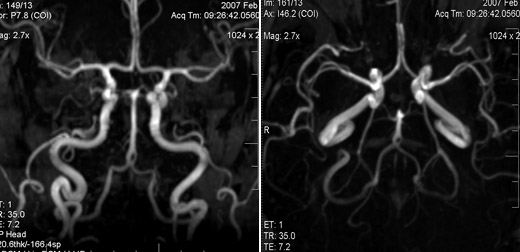

Одним из самых популярных методов обследования сосудистой системы считается ангиография. Эта методика предполагает введение в кровь пациента специального контрастирующего вещества. После того как оно равномерно распределится по всем артериям, делается рентгеновский снимок. На нем хороши видны все патологии.

Такое обследование может проводиться при помощи обычного рентгенографа или под контролем компьютерной томографии. Контрастирующее вещество полностью безвредно для человека. Спустя определенное время оно полностью выводится из организма естественным путем.

Для определения точного расположения и состояния артерий применяют также компьютерную томографию. Такое обследование проводится с применением рентгеновского облучения. И хотя доза облечения крайне мала, этот диагностический метод нельзя назвать полностью безопасным для здоровья.

Для исследования состояния сосудов в медицине используется метод ангиографии. Наиболее доступным способом диагностики считается транскраниальная доплерография, позволяющая оценить кровоток в мозговых артериях. Такой метод имеет большое количество преимуществ, потому что позволяет оценить состояние просвета сосудов, скорость и направление кровотока. Для постановки диагноза используется комплексное обследование, оценивающее все критерии строения артерий и характеристику кровоснабжения в них.